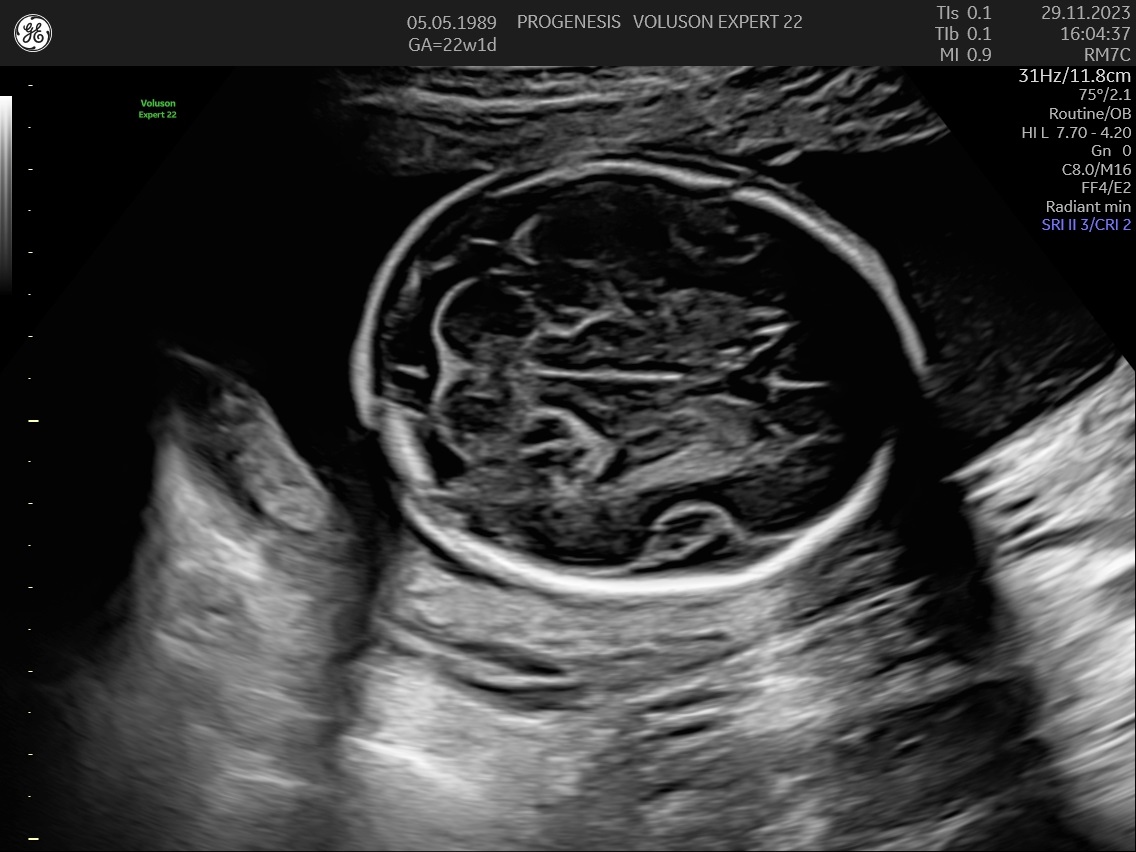

Υπερηχογράφημα Β΄Επιπέδου (20-24 εβδομάδων)

α) Η λεπτομερής αξιολόγηση της εμβρυϊκής ανατομίας, όπου αναγνωρίζονται τυχόν ανατομικές ανωμαλίες.

γ) Ο έλεγχος της ανάπτυξης του εμβρύου, του πλακούντα, του ομφαλίου λώρου και του αμνιακού υγρού.